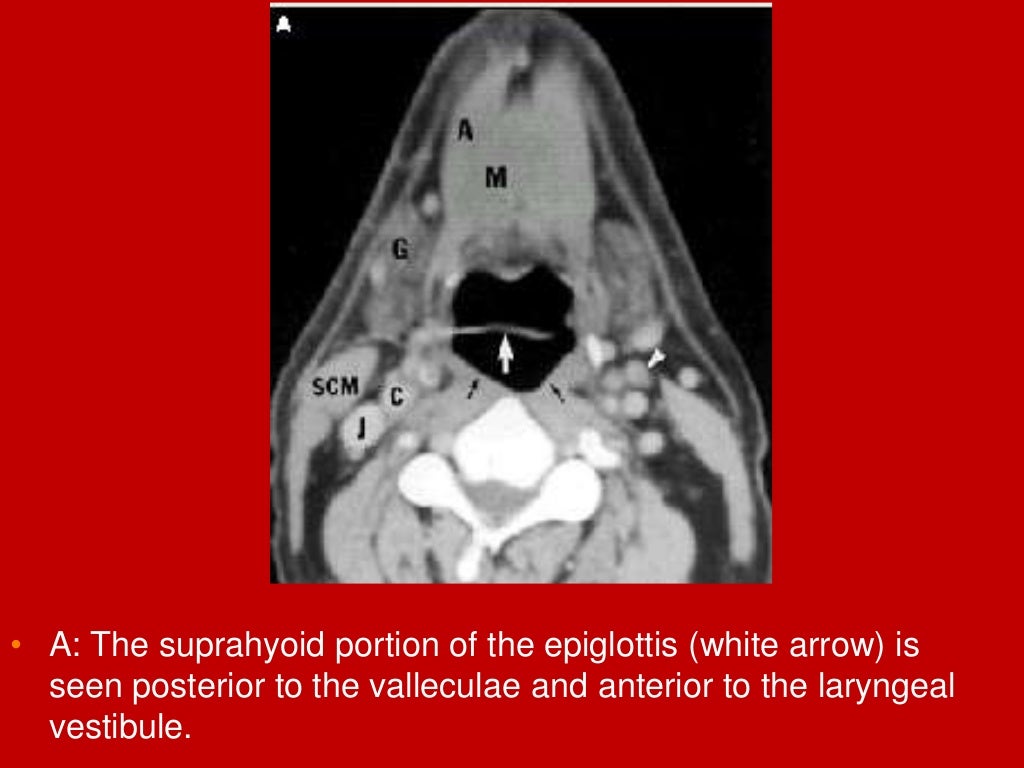

Mri Anatomy Larynx . It acts as a critical connection between the oropharynx above and the trachea below serving essential functions such as respiration, phonation and preventing aspiration. The larynx is a mucosa lined tube supported by a cartilaginous and muscular framework ably supported by multiple ligamentous and membranous structures. This chapter begins with a section on anatomy, including the normal appearance in the various imaging planes. (a) ct image of the soft tissue window on the sagittal plane of larynx; The larynx consists of a cartilage skeleton, as well as internal structures that are divided into three subsites,. The aim of this paper is to give a comprehensive radiological overview of larynx and hypopharynx complex anatomy, combining in vivo images,. A brief discussion of the technical. Provides a detailed review of radiological anatomy of the larynx. Ct and mri images of the sagittal plane of larynx. Mri is rarely used for laryngeal imaging, but may be valuable when assessment of laryngeal cartilage invasion is of critical importance. Presents imaging findings in benign and malignant disease.

Mri Anatomy Larynx The larynx consists of a cartilage skeleton, as well as internal structures that are divided into three subsites,. It acts as a critical connection between the oropharynx above and the trachea below serving essential functions such as respiration, phonation and preventing aspiration. Presents imaging findings in benign and malignant disease. This chapter begins with a section on anatomy, including the normal appearance in the various imaging planes. (a) ct image of the soft tissue window on the sagittal plane of larynx; The larynx is a mucosa lined tube supported by a cartilaginous and muscular framework ably supported by multiple ligamentous and membranous structures. Provides a detailed review of radiological anatomy of the larynx. Ct and mri images of the sagittal plane of larynx. The larynx consists of a cartilage skeleton, as well as internal structures that are divided into three subsites,. The aim of this paper is to give a comprehensive radiological overview of larynx and hypopharynx complex anatomy, combining in vivo images,. Mri is rarely used for laryngeal imaging, but may be valuable when assessment of laryngeal cartilage invasion is of critical importance. A brief discussion of the technical.